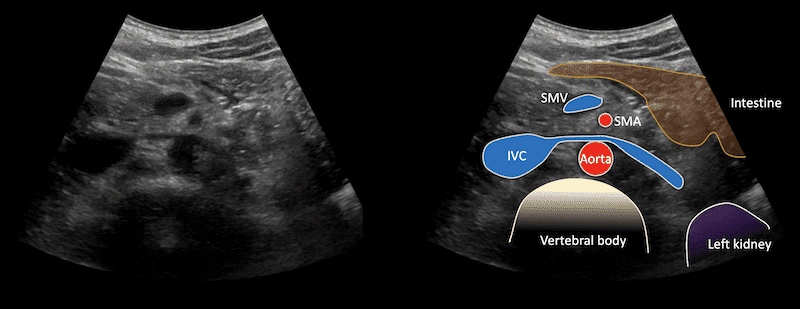

Immagine 3: Vista panoramica dell’emiscroto sinistro dal cranio al caudale.